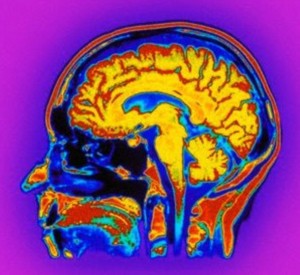

افزایش فشار داخل جمجمه، افزایش فشار نابینایی و درد تشنج از علائم تومور مغزی به شمار میآیند.

دکترمحمد علی اکبریان متخصص مغز در گفتگو با باشگاه خبرنگاران گفت: معمولا یک سوم بیمارانی که تومور مغزی دارند از سردرد رنج می برند.

وی گفت: از علائم تومور مغزی افزایش فشار داخل جمجمه (افزایش فشار باعث نابینایی یا اختلالات حرکتی) و درد تشنج را می توان نام برد.

وی در ادامه گفت: رشد تومور به محل قرار گیری آن بستگی دارد همچنین حجمی که تومور در مغز به خود اختصاص می دهد نیز در رشد آن موثر است، علائم تومور با توجه به محل قرار گیری آن فرق میکند در صورتی که تومور در مخچه شکل گرفته باشد بیمار دچار اختلال در تعادل میشود.

وی خاطر نشان کرد: برای درمان تومور مغزی باید نوع بیماری، محل تومور و تعدد تومور تشخیص داده شود که عمدتا درمان داروهای ضد صرعی و جراحی است.